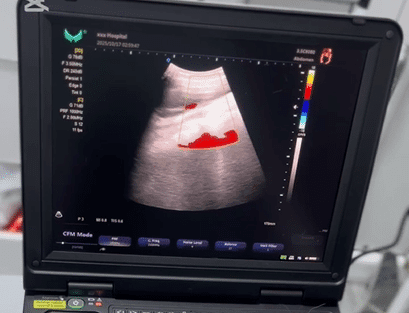

Le Doppler couleur permet d’afficher les flux sanguins en rouge et bleu, ce qui facilite l’analyse vasculaire, cardiaque et obstétricale.

🦵 Vaisseaux sanguins (Doppler vasculaire)

Le Doppler couleur et Power Doppler permettent :

- l’analyse des artères et veines

- l’évaluation de la perfusion sanguine

Pathologies détectables :

- thromboses veineuses

- insuffisance veineuse

- sténoses artérielles

- troubles circulatoires périphériques